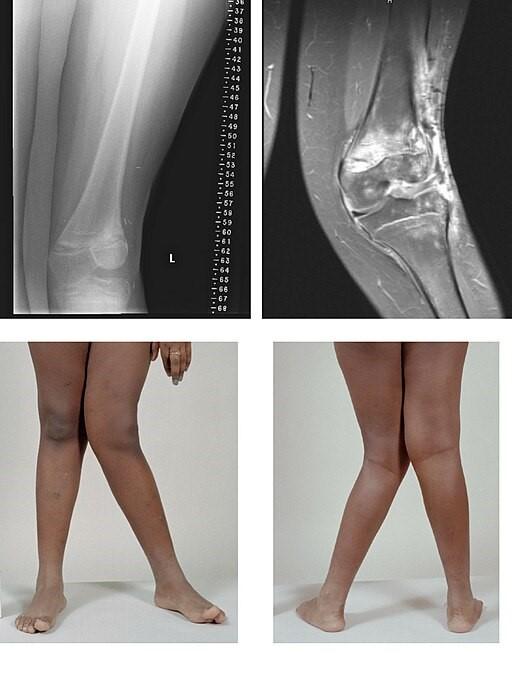

Valgus

© BioMed Central, CC BY 2.0, via Wikimedia Commons

By BioMed Central, CC BY 2.0, via Wikimedia Commons